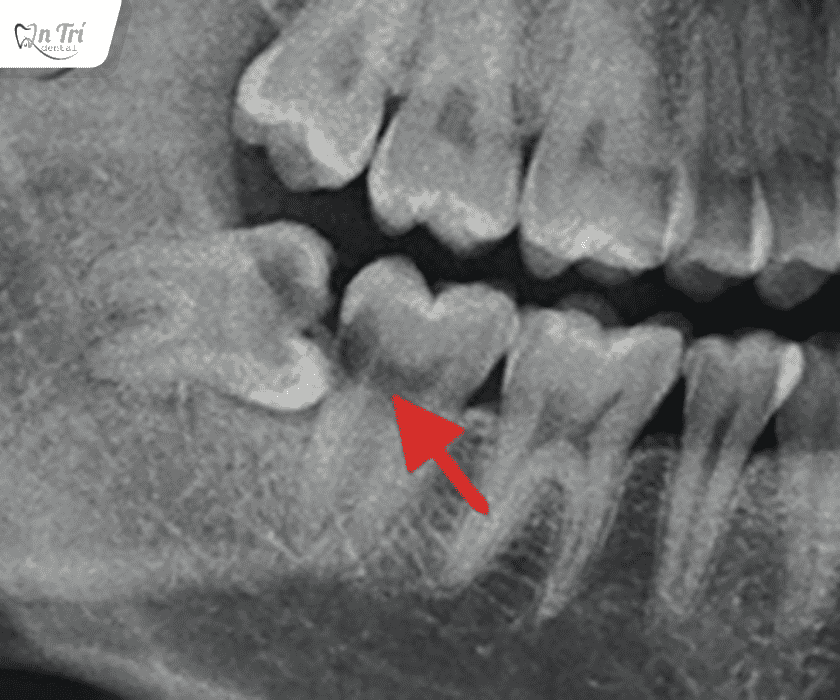

U nang răng khôn thường không có triệu chứng rõ ràng ở giai đoạn đầu. Hầu hết các trường hợp chỉ được phát hiện tình cờ qua phim X-quang khi bệnh nhân đi khám nha khoa định kỳ. Đến khi u nang phát triển lớn, nó có thể gây ra những triệu chứng như sưng to vùng má, lệch mặt, hoặc đau nhức âm ỉ.

Điều quan trọng nhất là bạn không thể tự mình chẩn đoán được u nang. Cách duy nhất để phát hiện sớm là thông qua việc khám nha khoa định kỳ và chụp phim X-quang. Bác sĩ sẽ dễ dàng nhận thấy hình ảnh u nang bất thường trên phim và có biện pháp xử lý kịp thời.

U nang răng khôn do biến chứng mọc kẹt

Điều quan trọng nhất là bạn cần thăm khám nha khoa định kỳ 6 tháng một lần. Việc chụp X-quang toàn hàm sẽ giúp bác sĩ phát hiện sớm bất kỳ bất thường nào, đặc biệt là sự tồn tại của u nang, để có biện pháp can thiệp kịp thời.